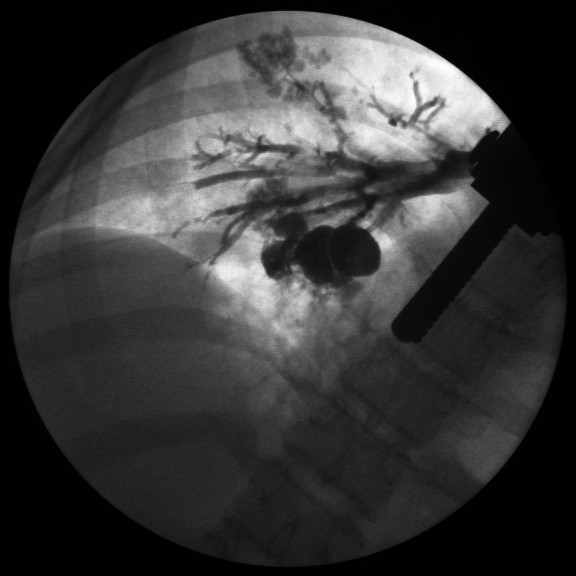

Фотографии и информация о бронхоскопии при туберкулезе